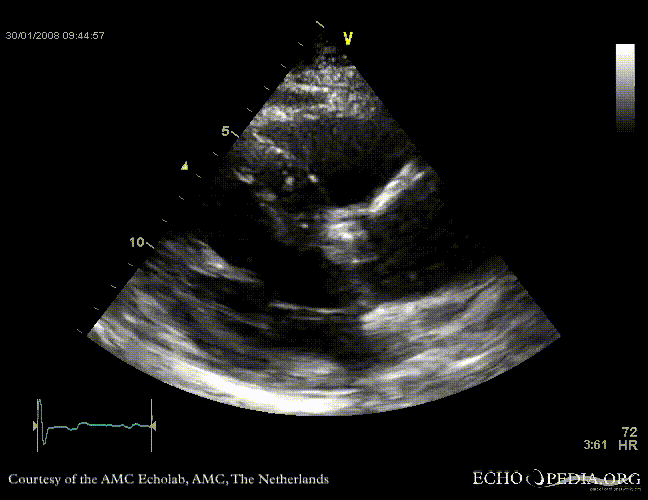

Aortic valve stenosis

J. Vleugels, AMC, The Netherlands